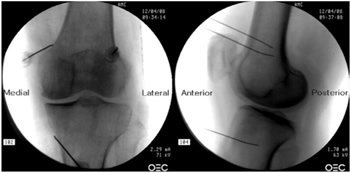

Radiofrecuencia de los nervios geniculados guiados por fluoroscopia

Para realizar una RFTNG guiados por fluoroscopia necesitamos una visión anteroposterior (AP) y lateral de la rodilla (Figura 2). Primero ubicamos al paciente en posición supina con una almohada debajo de la fosa poplítea (para que esté más cómodo) (16). Después de realizar asepsia y antisepsia de la rodilla, procedemos a ubicar los NG (Tabla II). El NGSL se encuentra avanzando la aguja de RFT hacia la confluencia de la diáfisis femoral lateral con el cóndilo femoral lateral en una visión AP y en un punto medio del fémur en una visión lateral. El NGSM se localiza avanzando la aguja hacia la confluencia de la diáfisis femoral medial con el cóndilo femoral medial en una visión AP y en un punto medio del fémur en una visión lateral. Por último, el NGIM se localiza avanzando la aguja hacia la confluencia de la diáfisis tibial medial con el epicóndilo tibial en una visión AP y en un punto medio de la tibia en una visión lateral (16,17).

Fig. 2. Proyección AP y lateral donde se observan las dianas terapéuticas usando fluoroscopia. Imagen tomada del artículo de Choi y cols. (9). Reproducido con la autorización de Jin Woo Shin.

Tabla II. Localización de los nervios geniculados guiados por fluoroscopia

Es muy importante tener una buena visión AP y lateral. En la proyección AP, la articulación tibiofemoral debe tener una anchura similar a ambos lados de la rodilla con el interespacio abierto (9). En la proyección lateral, debe existir una correcta superposición de ambos cóndilos femorales para realizar un bloqueo satisfactorio de los NGSM y NGSL (18).

La mayoría de autores toman las referencias descritas previamente para localizar estos nervios por fluoroscopia, excepto Fonkoué y cols. (18), quienes encuentran que las dianas terapéuticas del NGSM y NGSL (en una visión lateral) se encuentran en la unión del borde superior de sus respectivos cóndilos femorales con la corteza posterior de la diáfisis del fémur, y no en la mitad del espesor del fémur, como se describe clásicamente (9,10,13).

Dado que el éxito de la RFT de los nervios geniculados depende de la correcta ubicación de la punta de la aguja de RF (lo más cerca que se pueda al nervio), Know y cols. (17) demostraron con imágenes de resonancia magnética que los puntos que se usan clásicamente en fluoroscopia para la ablación de los tres nervios geniculados (NGSM, NGSL y NGIM) son correctos. Observaron que los NG pasan por la intersección formada por la línea diafisiaria y metafisiaria del fémur distal o de la tibia proximal (NGSL 92 %, NGSM 88 % y NGIM 100 %).